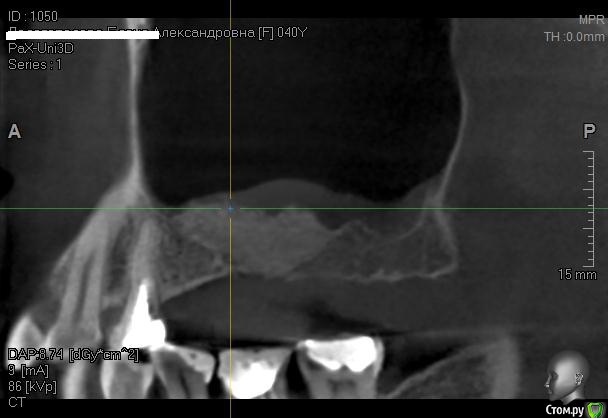

Kostoprav Опубликовано 12 июня, 2014 Автор Поделиться Опубликовано 12 июня, 2014 одновременно поставить -высоты кости не хватило ? 1-2 мм , я рисковать не захотел. 2 Ссылка на комментарий